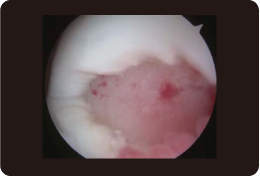

関節鏡による検査をおこなったところ、図のように一部陥没を伴う軟骨の欠損(約5.0cm2)が確認されました。

●1年後の移植箇所は写真のとおりで、移植された軟骨は、周りの健常な軟骨と同じくらいの硬さになっていました。